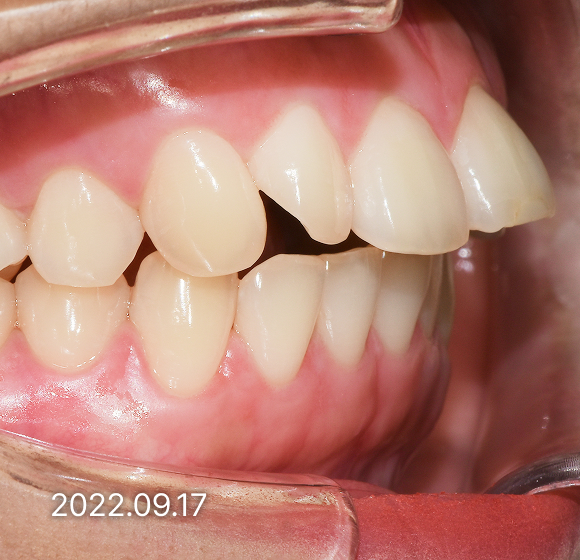

BEFORE / AFTER

전후 변화로 보는 치료사례

본 사진은 진심을담은치과교정과 치과의원에서

치료한 환자의 동일 인물 전·후 사진입니다.

개인의 구강 상태 및 관리 방법에 따라 통증 및 잇몸 염증,

턱관절 불편감 등의 부작용이 발생할 수 있습니다.

치료 전 치료 후

덧니, 삐뚤한 치열